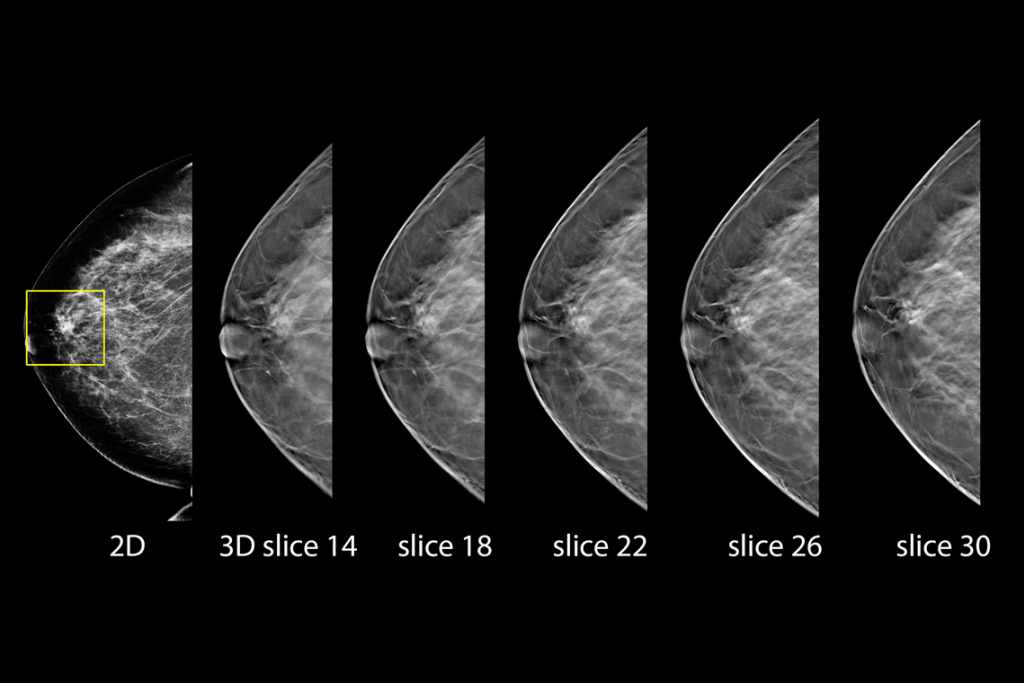

Klinische beelden van borstscanmammografie